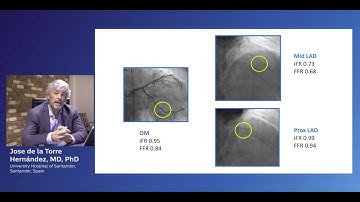

Case example: iFR Co-registration workflow